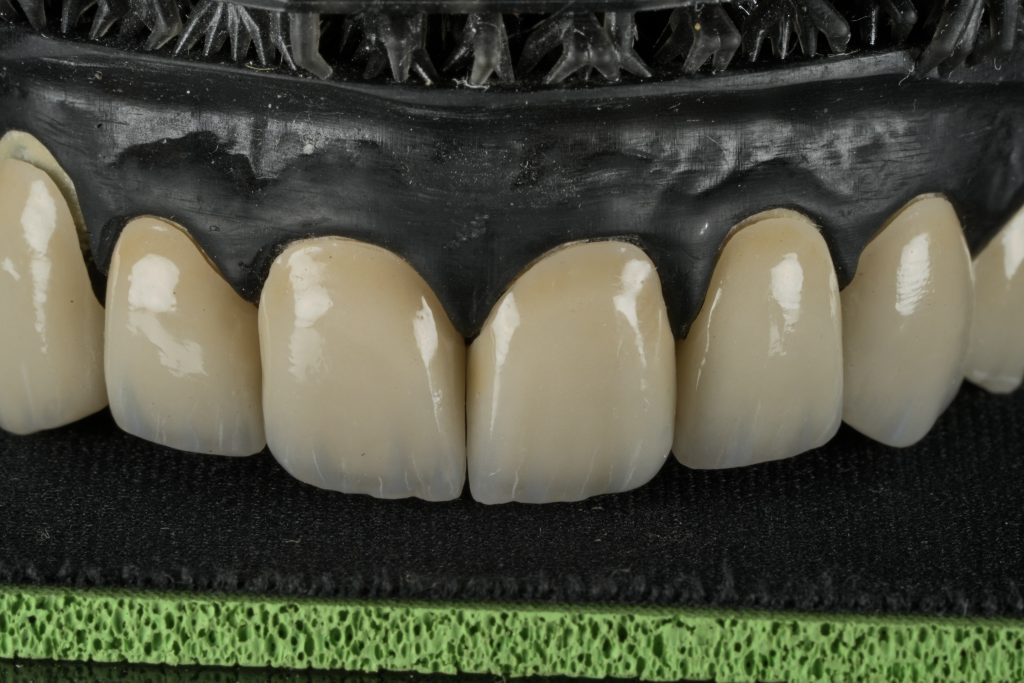

4️⃣ Laboratory Fabrication

IPS E-max Press veneers were pressed and characterized using micro-layered incisal ceramics for vitality and translucency. Surface texture and internal effects were customized to simulate natural perikymata and halo zones (Fig 3).